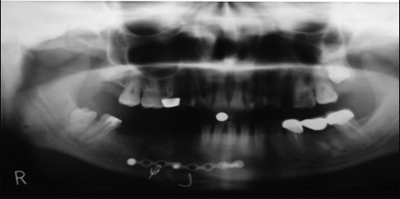

С появлением дентальной имплантации стало возможным отказаться от протезирования съемными и частично съемными протезами. В настоящее время, в предоперационном периоде, нами используется метод дентальной имплантации для замещения дефектов зубных рядов и восстановления прикуса больного, что дает возможность полного шинирования зубного ряда и получения стабильной фиксации во время хирургического вмешательства по поводу ложных суставов нижней челюсти (рис.1-5).

Рис. 2.